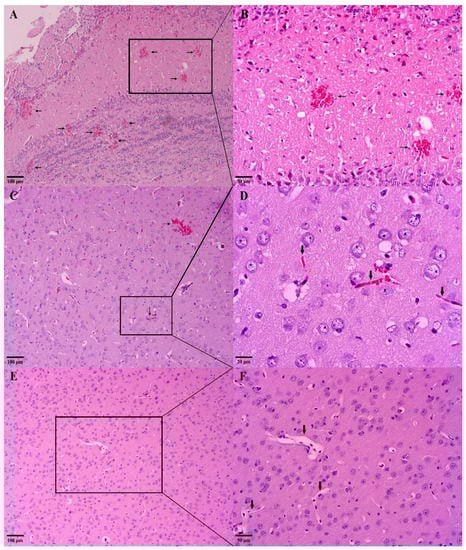

2.5.5. Macroscopic and Histological Analysis of the Brain